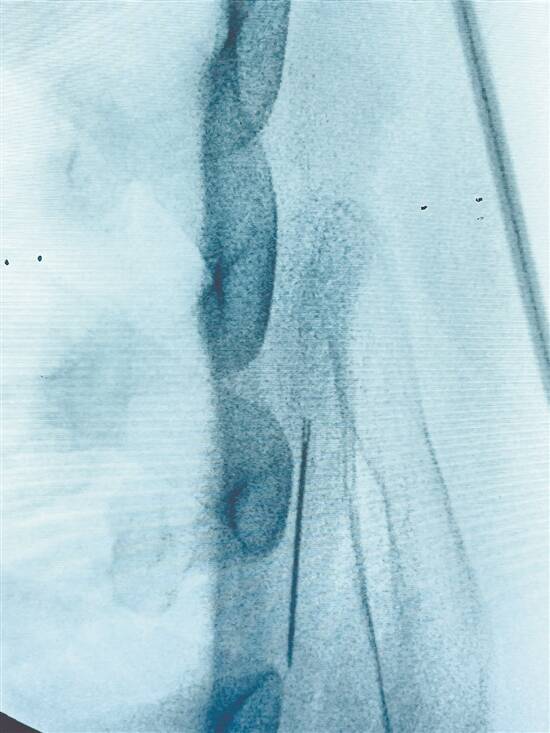

CT显示缝衣针已深入患者背部肩胛骨内侧面与肋骨间 |

文/图 羊城晚报记者 梁正杰 通讯员 胡会 李爱玲 邢莹 许梓筵 近日,佛山市民陈强(化名)被家人发现身上“藏”针,紧急送医院诊治,经过佛山复星禅诚医院(下称“禅医”)胸外科团队的手术治疗,从患者体内取出一根约4厘米长的缝衣针,为其解除了身体隐患。 缝衣针刺入体内数日已移位 陈强今年67岁,数天前他在卧倒时感觉左背部疼痛不适。因为此前他曾中风,有肢体感觉功能障碍等中风后遗症,短暂轻微的疼痛并未引起他的重视。家人为其洗澡时,发现背部有一条缝线。陈强的家属回忆起曾遗留一根缝衣针在床板上,他的症状疑似被缝针刺入身体。家属随即陪同陈强就医。 禅医胸外科主任宋长山接诊了陈强,并为其作进一步检查。胸部CT显示,陈强身上确有缝衣针,且缝衣针已深入其背部肩胛骨内侧面与肋骨间。由于缝衣针已刺入患者背部数天,随着患者上肢及背部肌肉运动,皮下缝线已脱落,缝针已移位,需马上取出。 “异物进入人体,可随肌肉、呼吸、心跳等运动游走。患者体内的缝衣针已接近胸腔,如进入胸腔,刺穿肺部或心脏大血管,将引起严重后果。”宋长山表示,必须为患者紧急开展手术,取出缝衣针。 精准定位取出4厘米长缝衣针 比起大海捞针,体内手术取针,不只是艰难,还很危险。宋长山介绍,缝衣针在手术中有可能进一步移位,掉进胸腔,这样寻找这根针的难度更大,也更危险。缝衣针若在胸腔内,或会刺伤心肺部大血管等,引起大出血,危及患者性命。 刻不容缓!宋长山团队随即制定手术方案,为患者取针“拆弹”。术前胸部CT发现缝衣针已深入患者背部肩胛骨内侧面与肋骨之间,以宋长山为首的手术团队,在全麻下为陈强实施左侧胸壁缝衣针取出术。手术看似简单,但由于肩胛背部肌层肥厚,且缝衣针针径细小,已移位到肩胛骨与肋骨之间,想要成功取出并不容易。为将局部损伤降到最小,术中宋长山根据解剖关系逐层切开,尽可能减小切口进行探查。由于针径细小,医生不能用手指去触摸其位置,以防扎伤发生交叉感染,只能用钳子夹出。由于肩胛骨的遮挡,难以看到缝衣针具体位置,于是术中宋长山使用C臂机精确定位,再将这支长约4厘米的缝衣针完整取出。 宋长山表示,入院时发现线在患者皮肤外面、针已经游走,线端可能因针游走的力量或者加上组织液溶解断裂,线尾端貌似留在皮肤层,但恰恰这样让人产生错觉以为针和线是一起的,这样会放松警惕让患者更危险。 宋长山提醒广大市民,如果异物进到身体的任何部位都要迅速就医,因为异物在进到身体以后,随着人体肌肉、关节的运动,异物就会在身体里游走,如果游走到心脏大血管,或其他重要神经部位都会造成二次伤害。